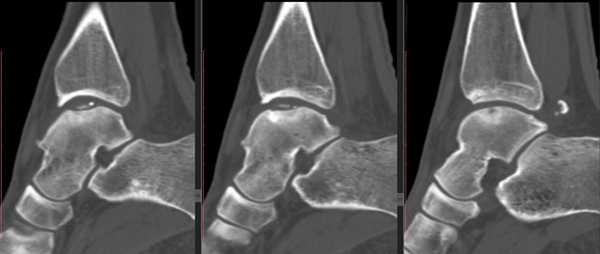

МРТ является ценным инструментом в комплексе диагностики ОХПТК для оценки отека костной ткани, а также выявления скрытых повреждений субхондральной кости и хрящевого покрытия, которые могут быть пропущены при стандартных рентгенограммах или даже КТ. МРТ – самый лучший инструмент оценки для определения стабильности и жизнеспособности фрагмента таранной кости при его отслоении и эта информация может быть решающей в тактике выбора того или иного метода хирургического лечения. Однако, для определения размеров отслоившегося фрагмента таранной кости наилучший метод КТ, так как данные размеров по МРТ могут не соответствовать действительности в сторону переоценки последних. Hepple с соавторами изучив многочисленные данные МРТ диагностики разработали систему классификации ОХПТК на основе этого метода (Табл. 2) [23]. Однако, наиболее широко принятая система классификации, основанная на КТ-это классификация Ferkel и Sgalione (Табл. 3; Рисунок 4) [24]. Классифицировать ОХПТК также возможно выполнить интраоперационно, на основе артроскопических данных о состоянии остеохондрального поражения. Наиболее широко используется система Ferkel/Cheng (Табл. 4) [25], эта система классификации, в отличие от обычных рентгенограмм, КТ и МРТ, лучше всего взаимосвязана с исходами лечения пациентов.

Для предоперационного планирования, однако, предпочтительно использование компьютерной томографии (КТ). КТ включает исследование с шагом 0,5 мм и ЗD реконструкцией поврежденного сустава. МРТ полезно для диагностики сопутствующих повреждений мягких тканей (мышц, связок и сухожилий).

I стадия: небольшой компрессионный перелом.

II стадия: неполный отрыв фрагмента.

III стадия: полный отрыв фрагмента с его смещением.

IV стадия: смещенный фрагмент.